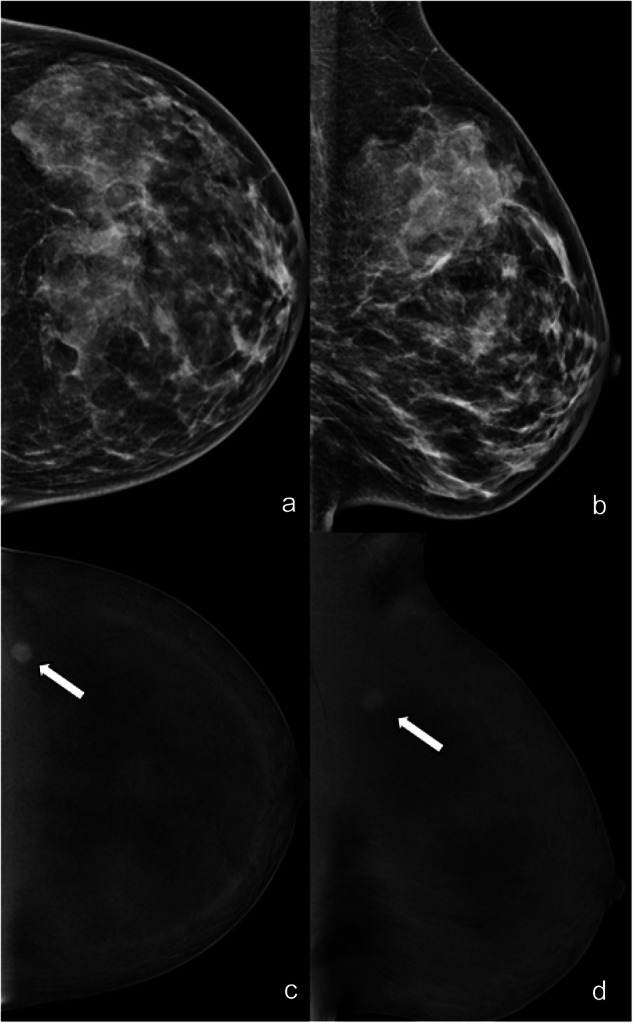

Fig. 2.

LE (a, b) and RC (c, d) CEM images of the left breast of a 35-year-old patient. The three readers evaluated in separate sessions ACR density (d, unanimously); type of lesion (mass for two of the three readers, asymmetry for the third); presence/absence of associated architectural distortion (absence and unanimously) on LE images; type of enhancement (white arrows: mass, unanimously); and lesion conspicuity (high for two of the three readers, moderate for the third) and mass enhancement descriptors (mass shape round, mass margin irregular, mass internal pattern of enhancement homogeneous, unanimously) on RC images. Finally, they assessed LE BI-RADS (4 for two of the three readers, 3 for the third) and RC BI-RADS (5 for two of the three readers, 4 for the third). Histology was triple-negative breast cancer

The inter-agreement was substantial for the type of enhancement on RC images (no enhancement, mass, non-mass, enhancing asymmetry) (ĸ = 0.664, Table 2). There was a moderate agreement for lesion conspicuity (ĸ = 0.517). The overall agreement for mass enhancement descriptors was moderate for shape (ĸ = 0.523) and margins (ĸ = 0.566) and substantial for an internal pattern of enhancement (ĸ = 0.618) (Fig. 2). The agreement for non-mass enhancement descriptors was fair for distribution (ĸ = 0.387) and moderate for an internal pattern of enhancement (ĸ = 0.415). The agreement for enhancing asymmetry descriptors was fair (ĸ = 0.247) (Fig. 3).